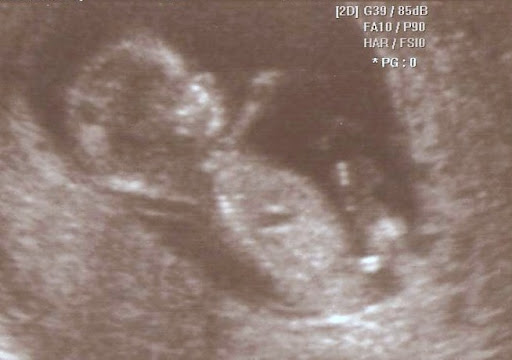

So it took me a while but I finally scanned the ultrasound pictures from that 2nd ultrasound I had during the week of 10/18.

These are from the Nuchal Translucency (NT) ultrasound on October 22nd. It was really cool to see the little one squirmin' around in there. In one of these pics (s)he's even waving! :)